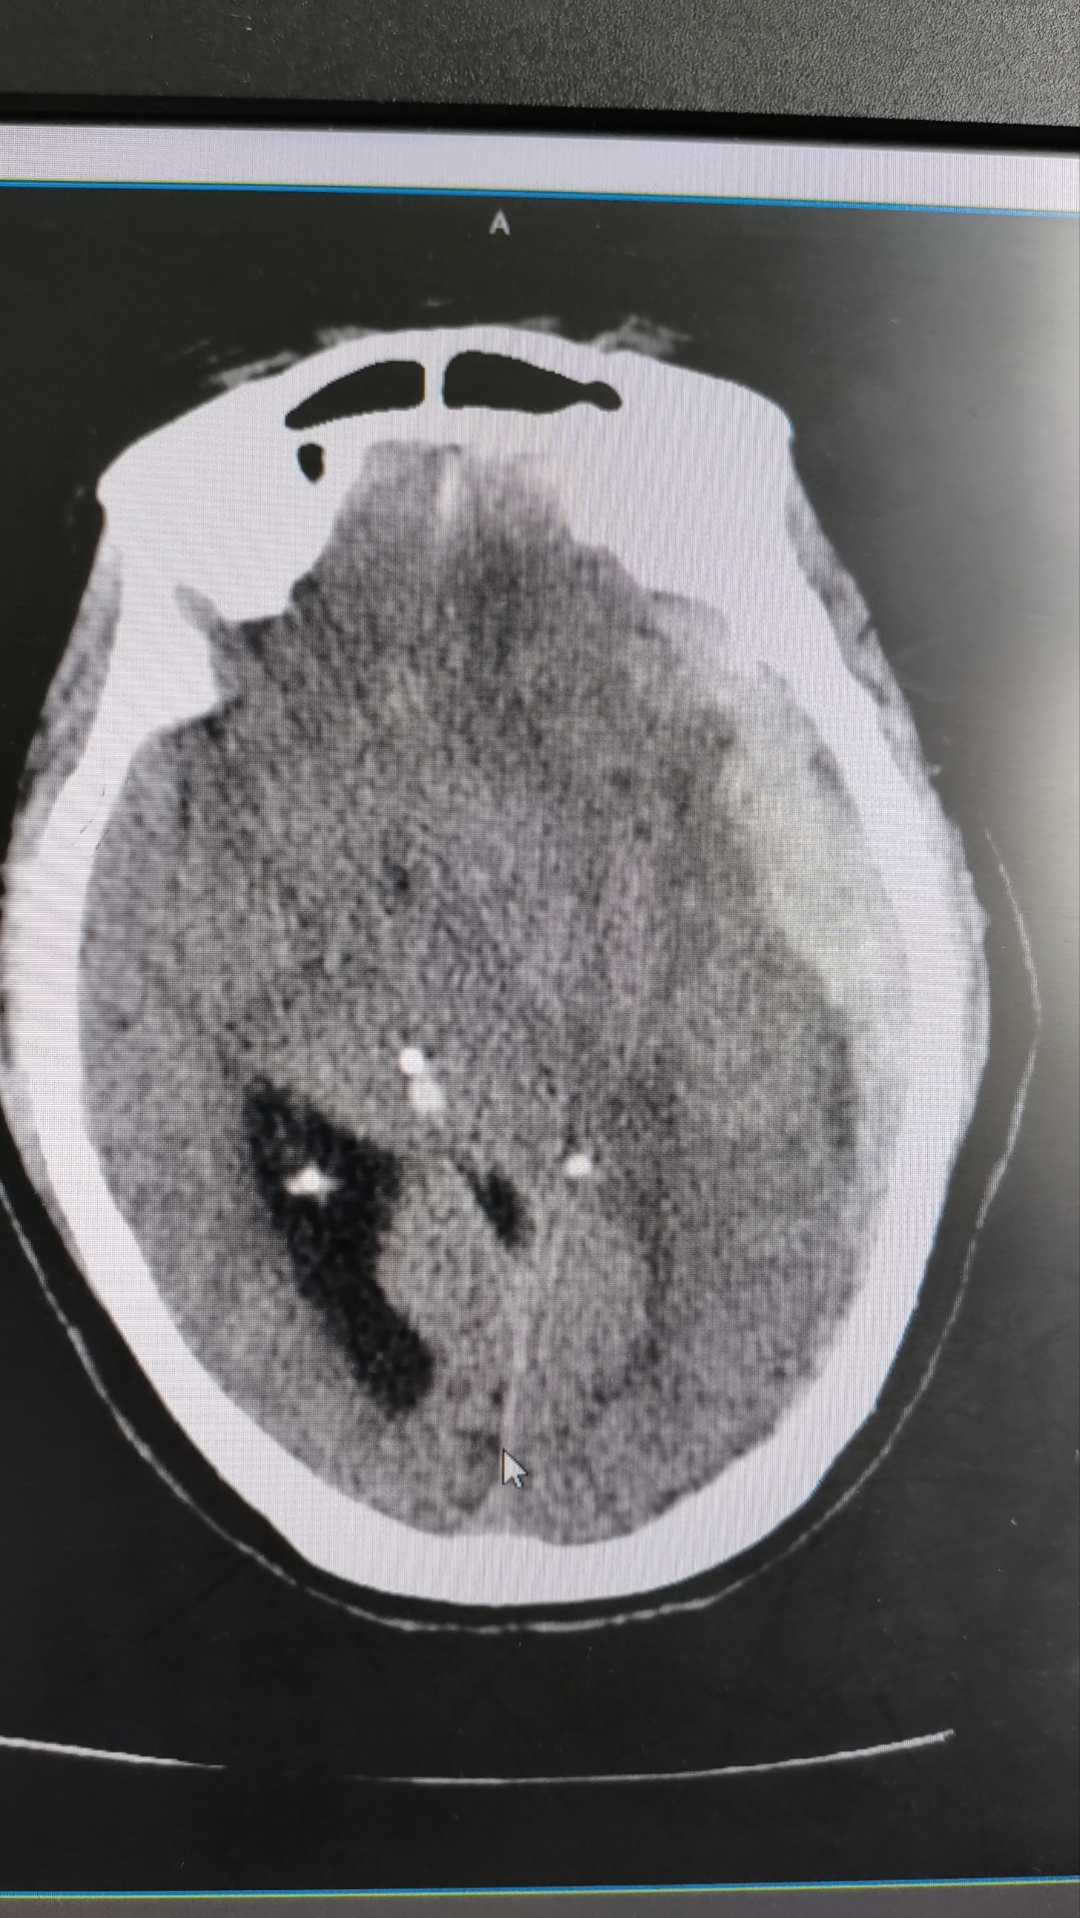

2、住院报销比例1报销范围A药费辅助检查心脑电图X光透视拍片化验理疗针灸CT核磁共振等各项检查费限额200元手术费参照国家标准,超过1000元的按1000元报销B60周岁以上老人在卫生院住院,治疗费和护理费每天补偿10元,限额200元2报销比例镇卫生院报销60%二级。

3、360岁以上老年人住院治疗费及护理费每天可以报销10元,最多报销200元4心脑电图X光透视拍片化验理疗针灸CT核磁共振等辅助检查项目最多报销200元这要看你的医保性质,还要看是否有异地就医备案山西的城乡居民医疗保险,异地就医备案成功河北省胸科医院三级报销医药费比例;北京胸科医院特别提示1我院实施“非急诊全面预约”就诊,您可以通过京医通微信公众号114预约挂号平台预约号源,并按预约时间来院就诊2医院门诊实行全天自助机取号,院内自助机均可正常使用3建卡时间上午730下午15 30建卡地点建卡处在住院二部门厅东侧4根据北京市统一规定,疫情期间来院就诊患。